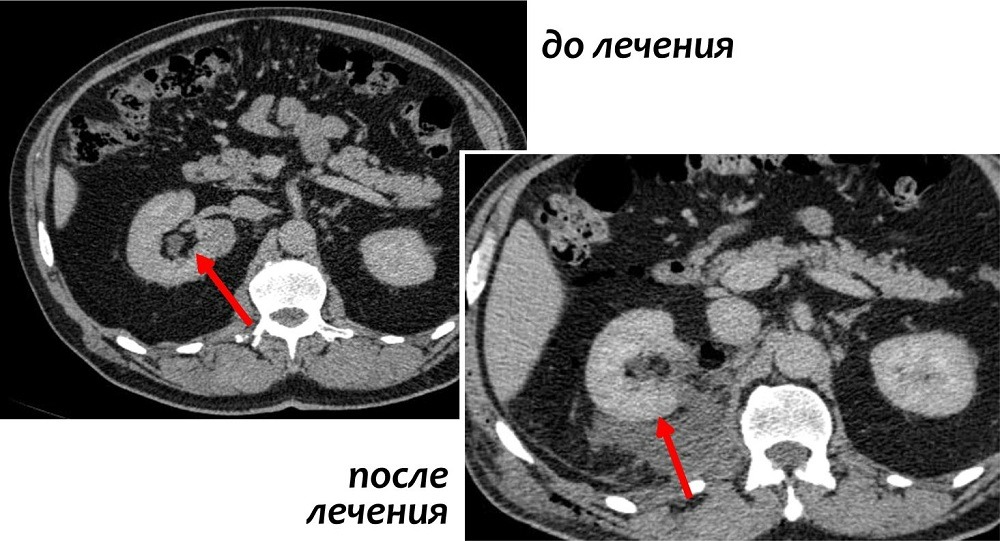

Резекция почки

В ходе данной процедуры, хирург удаляет только ту часть почки, которая содержит опухоль, оставляя оставшуюся ткань почки неповрежденной. В настоящий момент это предпочтительный метод лечения для пациентов с ранней стадией рака почки. Часто резекции вполне достаточно для удаления одиночных небольших опухолей до 4 см в диаметре.

Также этот метод может применяться у пациентов с бОльшими образованиями, до 7 см. Специалистами НИИ онкологии им. Н.Н. Петрова успешно выполнялись вмешательства на опухолях размерами 10 и более см, однако такие операции возможны только в отдельных случаях, с учетом анатомии опухоли.

Современные исследования показали, что отдаленные результаты у пациентов, перенесших резекцию почки, почти такие же, как у пациентов, у которых почка была удалена. Однако несомненным плюсом остается сохранение большей части почечной функции.